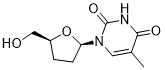

馬鞍山致研生物醫(yī)藥科技有限公司成立于馬鞍山市鄭浦港新區(qū)現(xiàn)代產(chǎn)業(yè)園。公司專(zhuān)注于生物小分子、醫(yī)藥中間體相關(guān)產(chǎn)品的研發(fā)和生產(chǎn),產(chǎn)品主要包括DNA亞磷酰胺單體、RNA亞磷酰胺單體、特殊單體以及按照客戶(hù)要求定制的RNA和DNA,并且公司提供定制合成等方面的研究服...

馬鞍山致研生物醫(yī)藥科技有限公司成立于馬鞍山市鄭浦港新區(qū)現(xiàn)代產(chǎn)業(yè)園。公司專(zhuān)注于生物小分子、醫(yī)藥中間體相關(guān)產(chǎn)品的研發(fā)和生產(chǎn),產(chǎn)品主要包括DNA亞磷酰胺單體、RNA亞磷酰胺單體、特殊單體以及按照客戶(hù)要求定制的RNA和DNA,并且公司提供定制合成等方面的研究服...